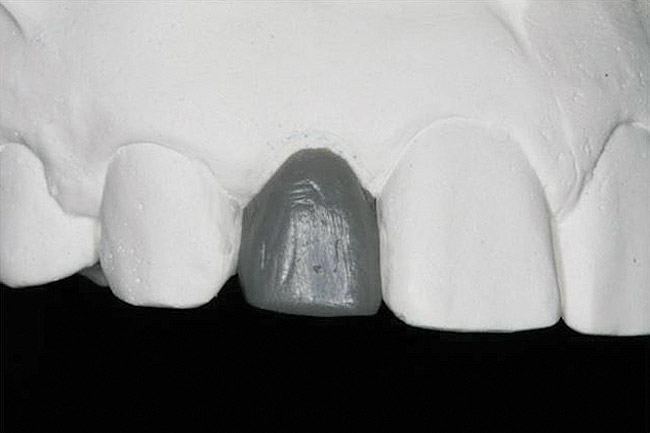

Figure 13   Exploiting study casts for planning single-tooth implant placement and restoration: Mounted study casts permit an estimation of available bone volume (Fig 13); measure the bound edentulous space inter-tooth dimensions (Fig 14); measure the available inter-arch dimension (restorative space) (Fig 15); and evaluate alveolar ridge/tooth relationships (distance from zenith represented by plastic stent to ridge crest) (Fig 16).

Figure 13